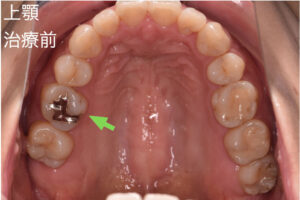

歯は一度削ったり抜いたりすると元には戻りません。できれば自分の歯を残したいと思う方が多いのではないのでしょうか。マイクロスコープを用いると、虫歯に汚染された部分を正確に捉えることができるため「なるべく歯を削らない」「なるべく神経を取らない」「組織を温存する」治療が可能となります。さらに虫歯の再発を防ぐ事にもつながるのです。

歯科治療は「虫歯に汚染された部位を削る」「歯の根の中の汚染された神経を除去する」など、細かい部位の細かな手技の連続です。肉眼(裸眼)では患部の細部まで捉えきれないため、マイクロスコープは歯科治療においては欠かせない器具だと考えております。マイクロスコープを活用すれば肉眼の約20倍の拡大率で治療ができるため、より精密な治療に繋げることができます。ただマイクロスコープは、すべての歯科医院に完備されてるわけではありません。歯科医院全体における普及率は約10%ほどです。マイクロスコープがない歯科医院では、レントゲン写真を参考に経験や勘に頼って歯科治療を行っているケースが少なくない状況です。その結果、虫歯の取り残しや歯の削りすぎ、汚染物質の取り残しなどが起こることがあるのです。マイクロスコープを使えば、虫歯に汚染された部分を正確に捉えて削ることに繋がります。

必要以上に患者様の健康な歯質を削ったり、虫歯を取り残して再治療をしたりするリスクが減るのです。ご自分の歯を活かしたキレイな歯をご提供することが可能となるのです。当院の院長は、PIFというマイクロスコープのグループに所属し、マイクロスコープの使用方法などのインストラクターとしても仕事をしております。

歯科用マイクロスコープとは、肉眼の約20倍まで拡大できる歯科用顕微鏡です。目に見えない部分にいたるまで、精密で正確な治療に繋げることができます。

当院ではほぼ全ての一般診療にマイクロスコープを使用した精密な治療を提供しております。